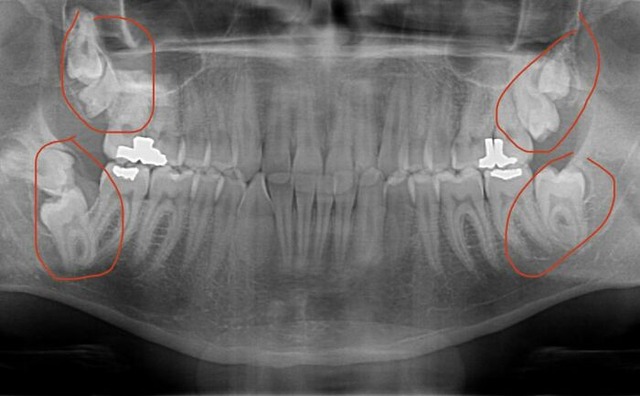

万国アノニマスさん

自分の歯根は本当に長かった

10

フックのようになってる親知らずを抜いた

手術を担当した医者も30年のキャリアでもワースト10に入ると言ってたし

割らずに抜いたのもワースト10のうちで唯一だと言ってた

万国アノニマスさん とんでもないな

万国アノニマスさん こんなの抜くとか無理だろ

自分には7本の親知らずがある

万国アノニマスさん なんて可愛そうな人なんだろうか

何かのタイミングでレントゲン等が撮れているなら出来る限り早めに抜かれるとよいと思います

前の方への歯の圧迫等で虫歯や健康な歯が刺激されるので